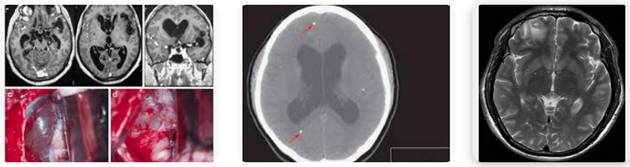

Hình 6. Một số thương tổn do ấu trùng sán dây lợn trên hệ thần kinh